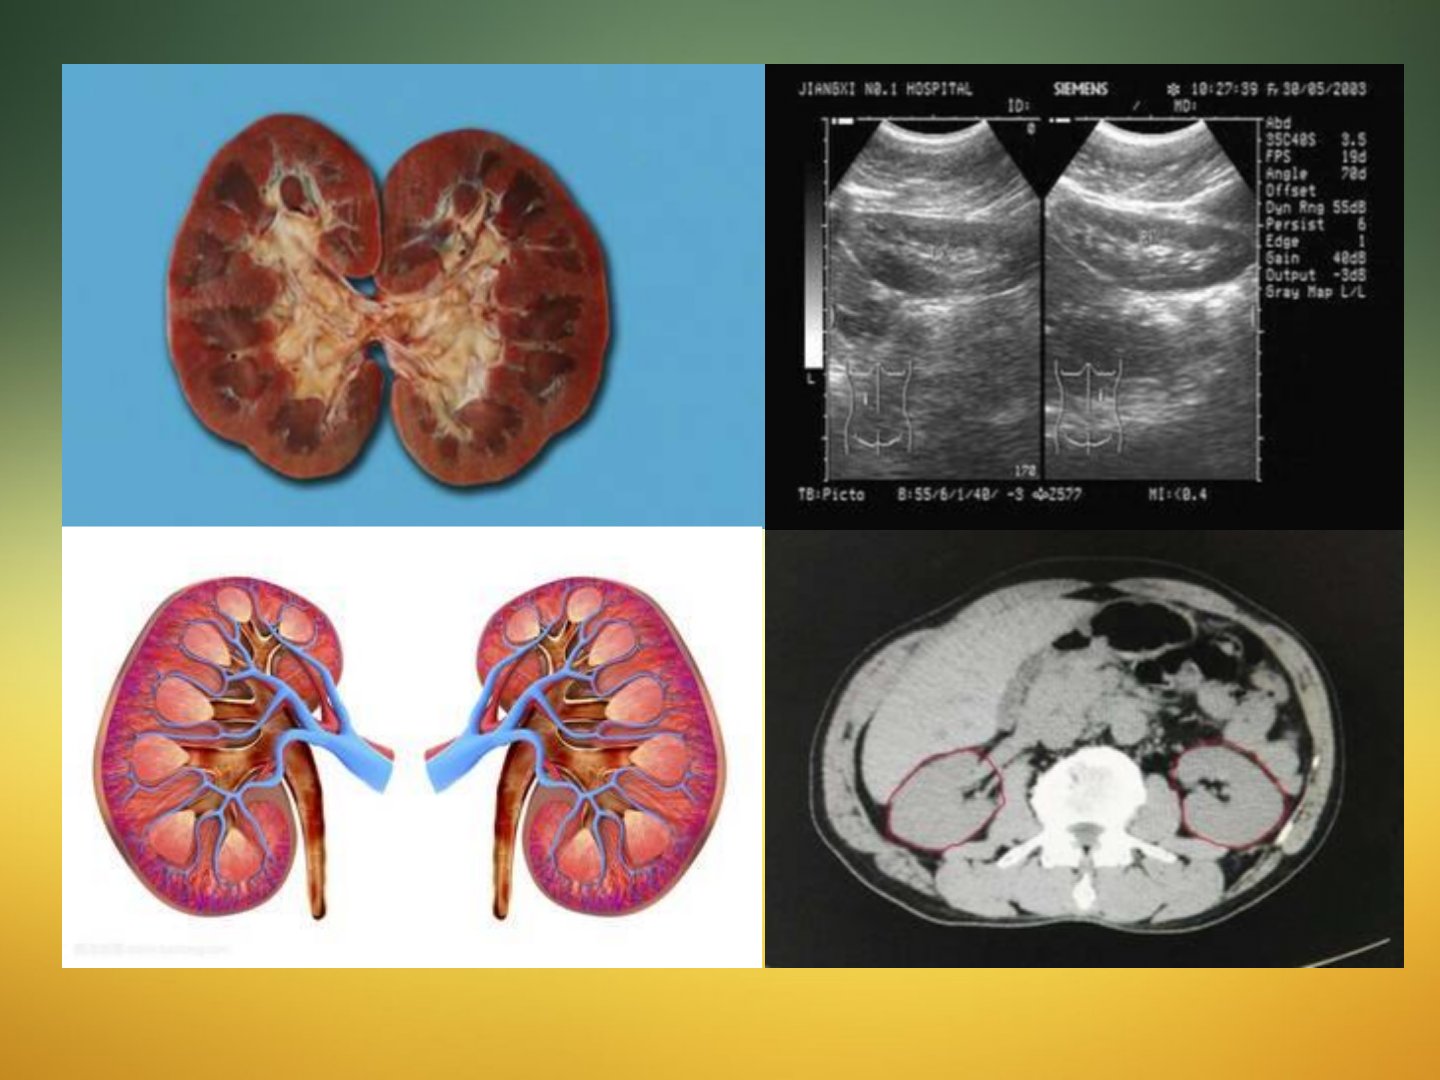

《肾脏Ca的超声诊断》摘要郭允鹏从多方面介绍肾脏Ca超声诊断。肾脏解剖上肾实质分皮质与髓质肾窦部含小盏、大盏等肾包膜由外到内有不同结构。肾脏肿瘤中胚胎瘤以肾母细胞瘤等常见实质性恶性肿瘤肾细胞癌最多肾盂恶性肿瘤多为移行上皮乳头状癌。肾细胞癌病理分型多样吸烟是其重要危险因子。肾实质恶性肿瘤中肾细胞癌临床表现多见于中老年人早期多无症状典型症状为间断性无痛肉眼血尿“肾癌三联征”出现多为晚期。其声像改变多样可通过Robson分期进行超声分期。鉴别诊断方面需与肾脏正常变异、小肾癌与肾良性肿瘤、囊性肾癌与肾囊肿、肝肿瘤等相鉴别。肾盂癌多为移行细胞癌临床表现早期多为无痛肉眼血尿声像改变多样。诊断时要调节合适深度用彩色多普勒观察包块注意静脉是否受侵小结节难鉴别时建议其他检查。